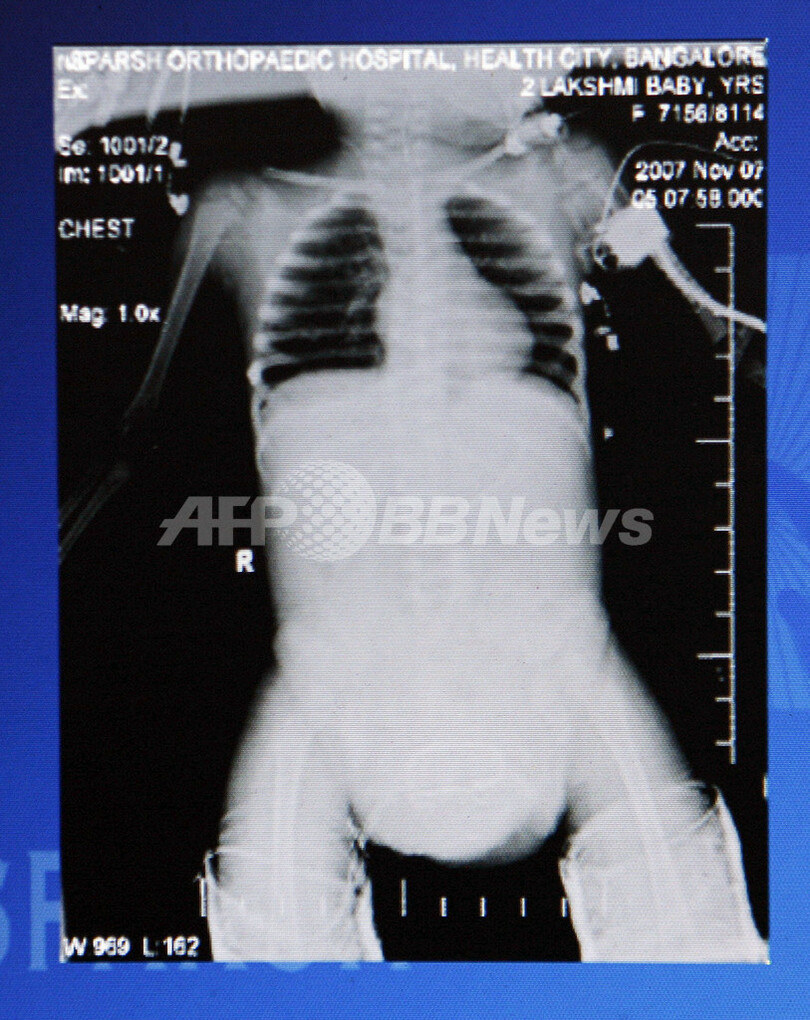

【11月7日 AFP】(11月9日写真追加)8本の手足を持って生まれた2歳の少女の四肢分離手術を行ったインドの医師団は7日、24時間以上に及ぶ手術が無事成功したと発表した。

4本の腕を持つヒンズー教の女神にちなんでラクシュミ(Lakshmi)ちゃんと名付けられたこの少女は、母胎内で発育を停止した双子の姉妹と結合して生まれた。結合双生児の中でも5万件に1件というまれなケースで、未発達だった部分から臓器なども受け継いでいるため手術は危険が伴うが、このままでは10代まで生きられないだろうと診断されていた。

この種のものとしてインド初の手術は、バンガロール(Bangalore)のSparsh病院で行われ、小児科や整形外科の専門医で構成する36人の医師団が執刀。余分な手足を切除して腎臓のうちの1つを残し、骨盤を再生した。